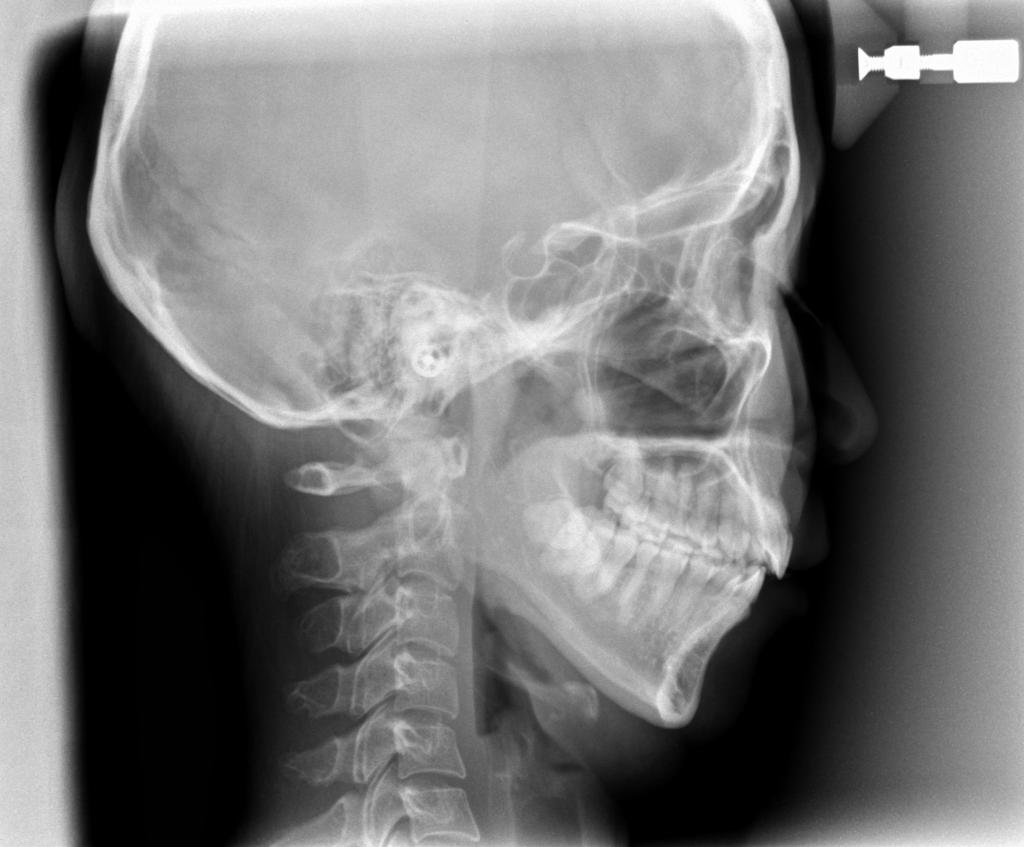

- 顎、顔の歪みの矯正治療

- 息がし難い

- 下顎前突(受け口)の方は、まれに治療中・治療後に下アゴが平均を著しく上回って成長することがあります。その場合、成人になって下アゴを後退させる手術が必要になる可能性があります。

- アゴが横にずれている場合(骨格性のタイプ)は、手術を伴う矯正治療以外では顔のゆがみは治せません。